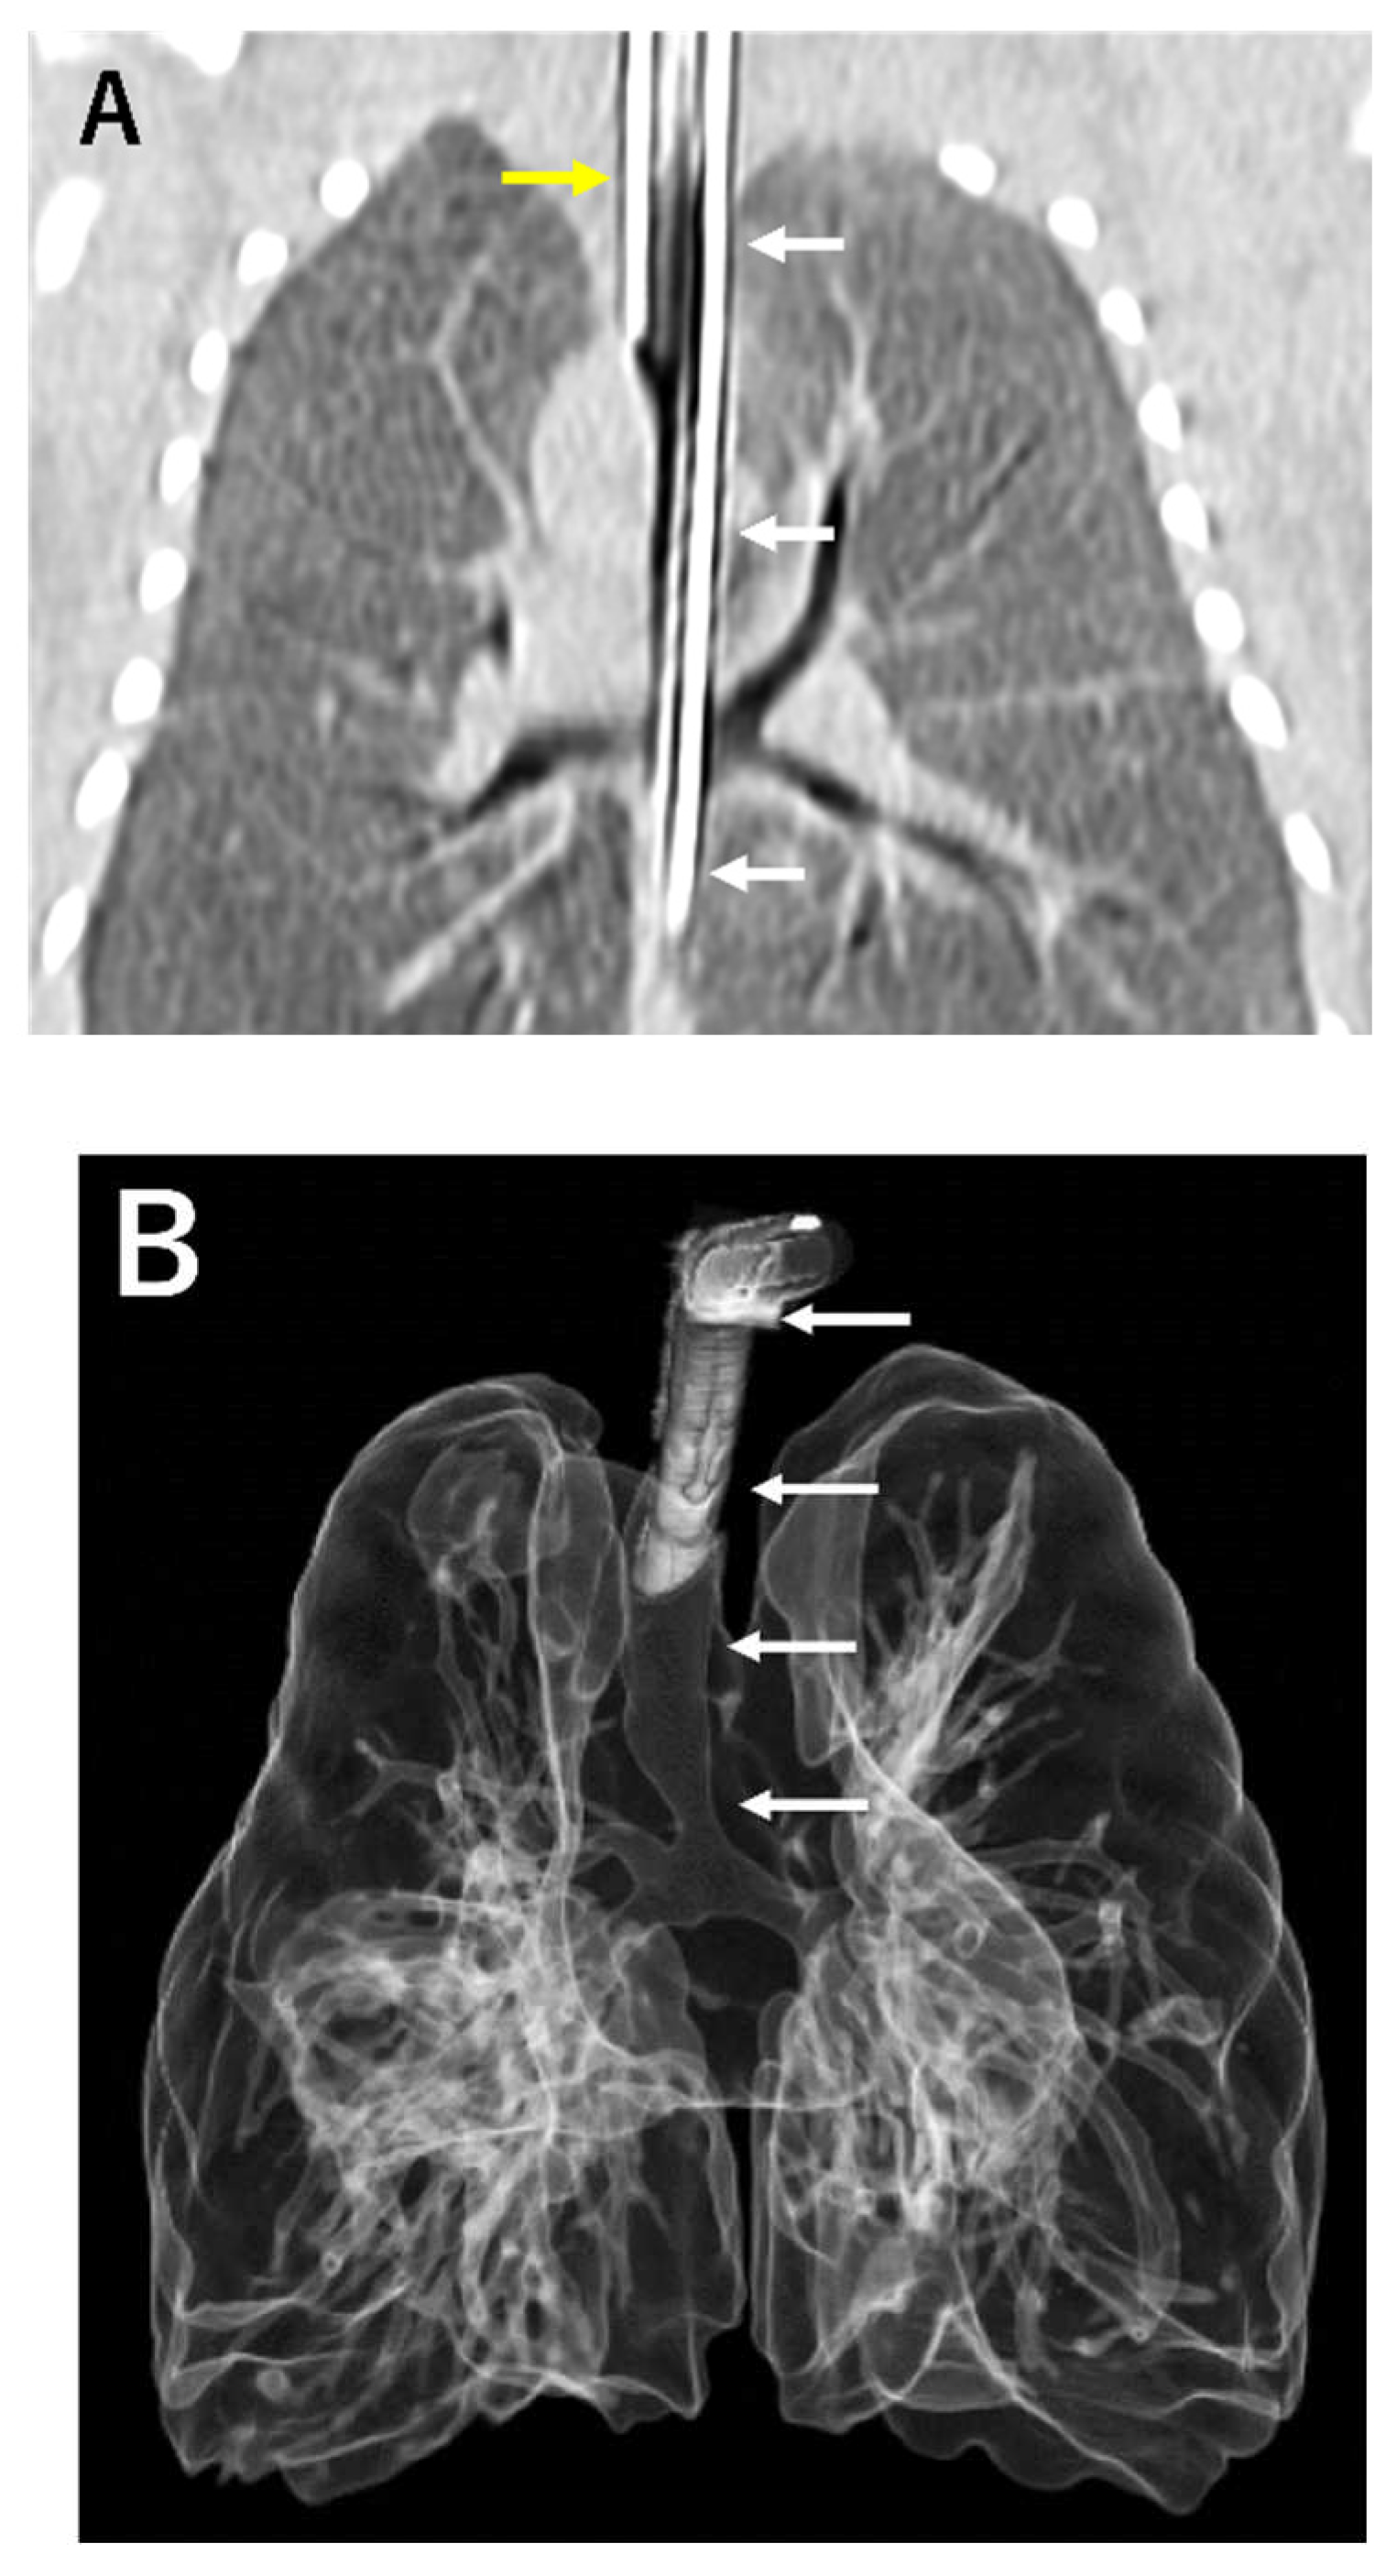

2. Case Description